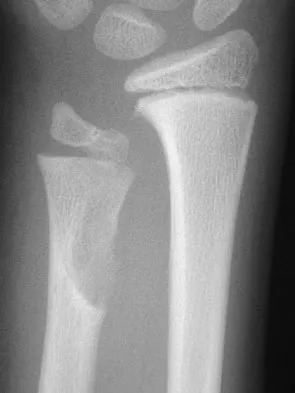

A previously asymptomatic 14-year-old girl sustained a twisting injury to her ankle. Radiographs are shown in Figures 2a and 2b. Management should consist of

Explanation

The radiographs show a well-defined, irregular, eccentric lesion in the distal tibia metaphysis with a thin sclerotic margin. The radiographs are diagnostic of nonossifying fibroma, a common entity in this age group and in this location. No further work-up is indicated. The patient was asymptomatic prior to the injury and the lesion is small and thus not worrisome for an impending pathologic fracture; therefore, no treatment is indicated beyond observation. The natural history of these lesions is to gradually ossify as the patient reaches skeletal maturity. Menendez LR (ed): Orthopaedic Knowledge Update: Musculoskeletal Tumors. Rosemont, IL, American Academy of Orthopaedic Surgeons, 2002, pp 69-75.